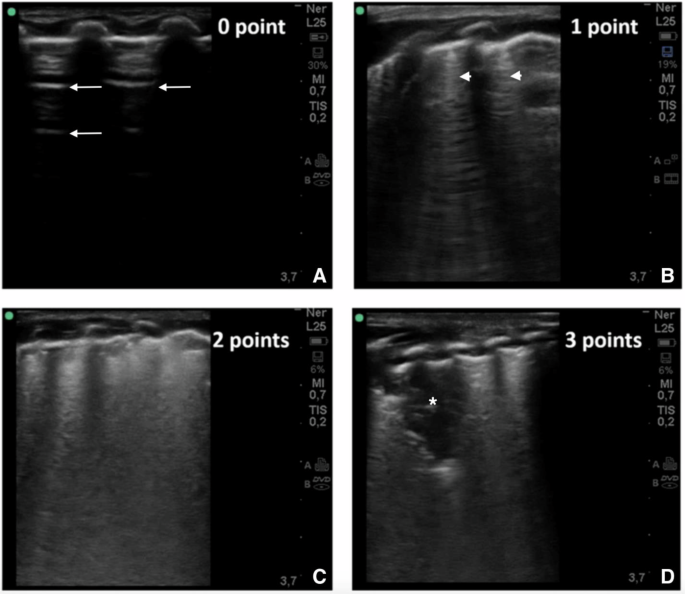

Lung ultrasounds were completed weekly beginning at 2 weeks of age by three trained sonographers (CM, RW, SM). Scans were completed with a commercial transportable ultrasound device (SonoSite SII) using a high frequency linear probe (13–6 MHz). The scanning protocol included five lung zones in each lung (anterior superior, anterior inferior, lateral, posterior superior, and posterior inferior: as shown in Fig. 1 in Zong et al.) [16]. Anterior and lateral zones were assessed in the supine position, while posterior zones were assessed in the lateral decubitus position. Two, 3–5 s cine clips were taken of each lung zone and stored for later analyses. The patient’s position was recorded (supine, prone or lateral decubitus) one hour prior to the scan. Aeration in each lung zone was scored from 0 to 3 points (total score ranging from 0 to 30), using a validated extended lung ultrasound scoring protocol [17]. The sum of the total score serves as an index for the severity of lung disease. The LUSSc was assigned as follows: 0 indicates A-pattern (defined by the presence of only A lines); 1, B-pattern (defined by the presence of ≥ 3 well-spaced B-lines within the frame); 2, severe B pattern (defined as the presence of coalescent B-lines with or without consolidation < 1 cm in depth from the pleural line); and 3, coalescent B-lines with extended sub-pleural consolidation (Fig. 1). Lung ultrasound findings have been shown to correlate closely with extravascular lung water measured by transpulmonary thermodilution [18]. Per multiple prior studies, A-lines represent reflections of the pleural line that are visible when ultrasound waves diffuse through a non-obstructed air-filled lung. B-lines occur when there is increased lung density filling the interstitium and/or alveolar space [16,17,18,19,20].

A 0 points; normally aerated lung with A line pattern (A-line denoted by arrows) that represents reflections of sonographic waves off the pleura in a non-obstructed air-filled lung. B 1 point; mild interstitial syndrome with non-confluent B-line pattern (B-line denoted by arrow heads) representing transmission of sonographic waves through lung parenchyma with increased density filling the pulmonary interstitial and/or alveolar spaces. C 2 points; severe interstitial syndrome with confluent B-line pattern with or without evidence of consolidation < 1 cm in depth from the pleural line. D 3 points; extensive lung consolidation (Denoted by asterisk) with coalescent B-lines with sub-pleural consolidation ≥ 1 cm in depth from the pleural line extending into the parenchyma.